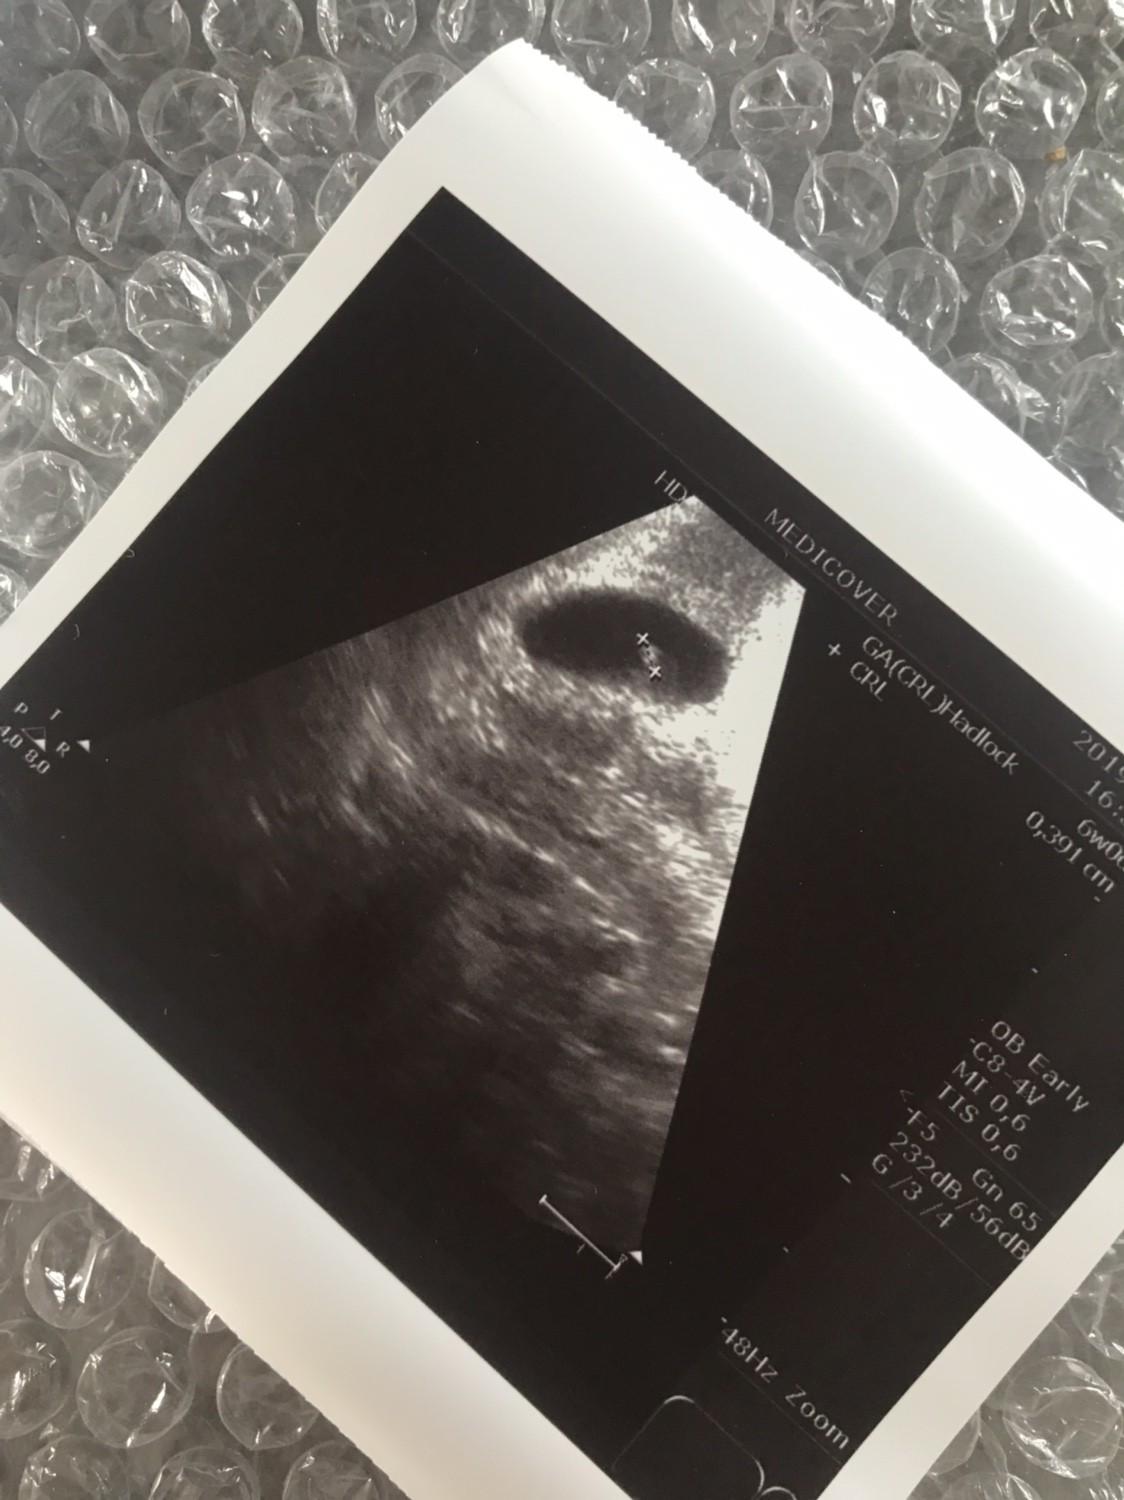

11.07 miałam @test ciążowy wychodził mi pozytywny już w 24dc. Zrobiłam bete: 26dc 95, 28dc 294, 31dc 1148 (godz 18.00), 33dc 2250 (godz 8:30). Wczoraj byłam u lekarza, według om byl to 5tc+5 a z usg 5tc+2. Widoczny był tylko pęcherzyka i zmartwilam się że nic więcej nie zobaczył mimo że owulacje miałam w 13/14dc. Mam przyjść za tydzień, ale trochę się podlamalam. Czy ktoś miał podobna sytuacje? Czy mimo wzrastającej wcześniej bety ich może się teraz ciąża nie rozwijać prawidłowo czy to za wcześnie na zarodek?